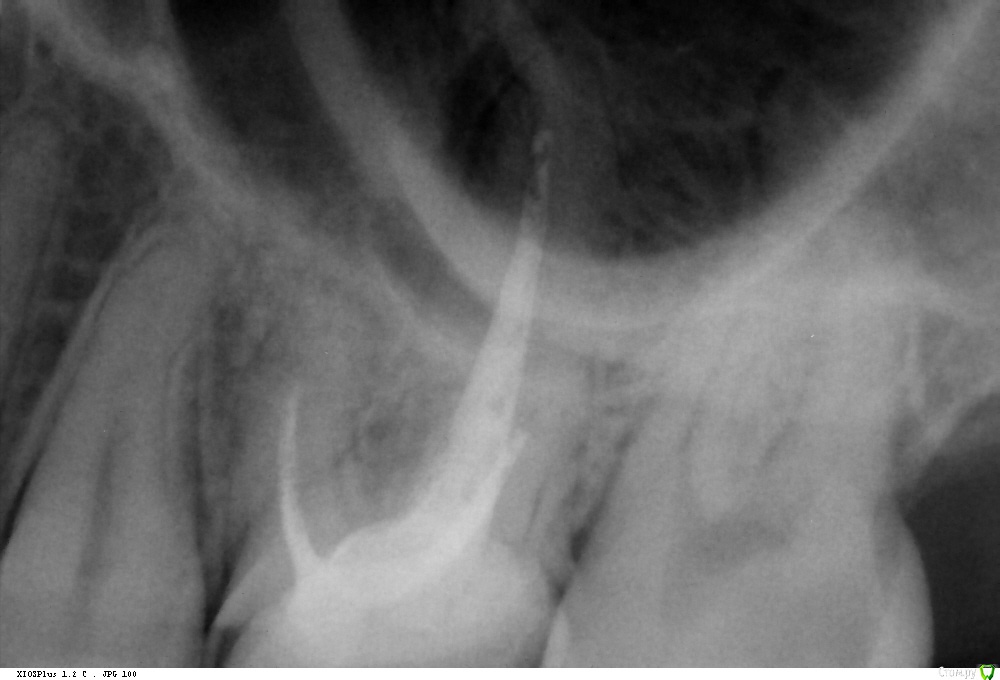

Где-то 3 недели назад эта шестёрка начала разрушаться и в какой-то момент откололся сразу большой кусок зуба. В результате осталось где-то 50% поверхности зуба. Какое-то время из-за этого болела десна, но это прошло довольно быстро. Я пошёл к стоматологам. Был у нескольких, на всякий случай. Сделал снимки (в том числе и 3D, но его я, к сожалению, пока приложить не могу, ибо оставил его дома на диске, выложу как приеду, если будет нужно, 2D снимки прикрепил). По снимкам все врачи нашли что-то плохое под зубом около пазухи (но не доходя до неё, пока, но говорят, что она довольно близко). Говорили разное: либо киста, либо воспаление.

Прикреплено:

2) Одиночный снимок - сделан месяц назад;